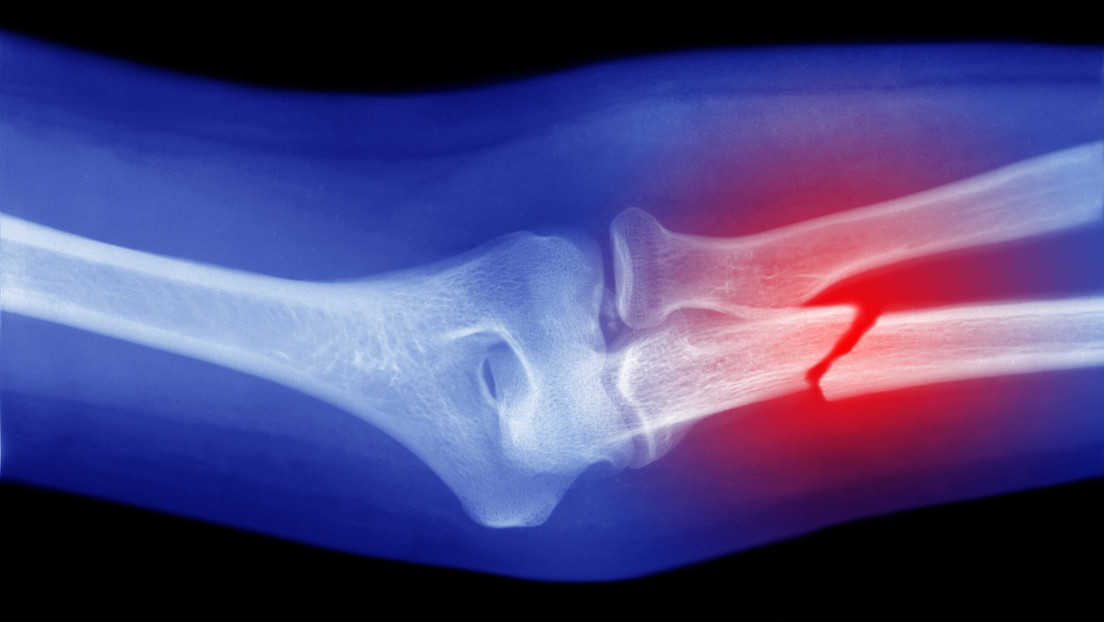

Científicos de la Facultad de Medicina Perelman de la Universidad de Pensilvania (EE.UU.) ha hecho un descubrimiento que podría facilitar la curación de fracturas, principalmente aquellas más complicadas. En modelos con ratones, los investigadores, liderados por el doctor Ling Qin, demostraron que un tipo de célula madre que se ha descubierto recientemente es capaz de transformarse en células óseas y conducir a una eficaz curación.

Este profesor de cirugía ortopédica y su equipo encontraron en el músculo esquelético —aquel unido a los huesos y que permite mover las distintas partes del cuerpo a través de su contracción voluntaria— unas células madre llamadas Prg4+ de tipo progenitor fibro-adipogénico (FAP). Descubrieron que, tras una lesión ósea, migran al callo de fractura (estructura temporal que se forma para guiar la curación) y allí se transforman en células óseas. Finalmente, restablecen la superficie ósea, detalla su estudio, publicado en la revista científica PNAS.

De este modo, las Prg4+ podrían ser la clave para la curación ósea tras fracturas graves, cuando el hueso y la piel se rompen y se produce una pérdida extrema de tejido. Debido a que en estas heridas la reparación no siempre es eficiente, los científicos creen que, de cara al futuro, se podría estimular su actividad dentro del cuerpo o introducirlas de forma activada "directamente en el lugar de la fractura para acelerar la curación ósea", señalan desde la Universidad de Pensilvania.

El mecanismo de comunicación cruzada entre los tejidos muscular y óseo revelado por Ling y sus colegas demuestra que en el tratamiento de las fracturas valdría la pena poner un énfasis adicional en los músculos cercanos al hueso afectado. Y quizás no solo en el caso de fracturas difíciles, como después de un accidente automovilístico o una lesión en el campo de batalla, sino en otras más comunes. "Esto podría tener un impacto real en áreas donde los músculos simplemente no son tan prevalentes, como la rodilla y el tobillo. También podría tener un impacto significativo en los adultos mayores, cuya masa muscular disminuye de forma natural y cuya cicatrización no se produce como antes", afirma Jaime Ahn, coautor del estudio.